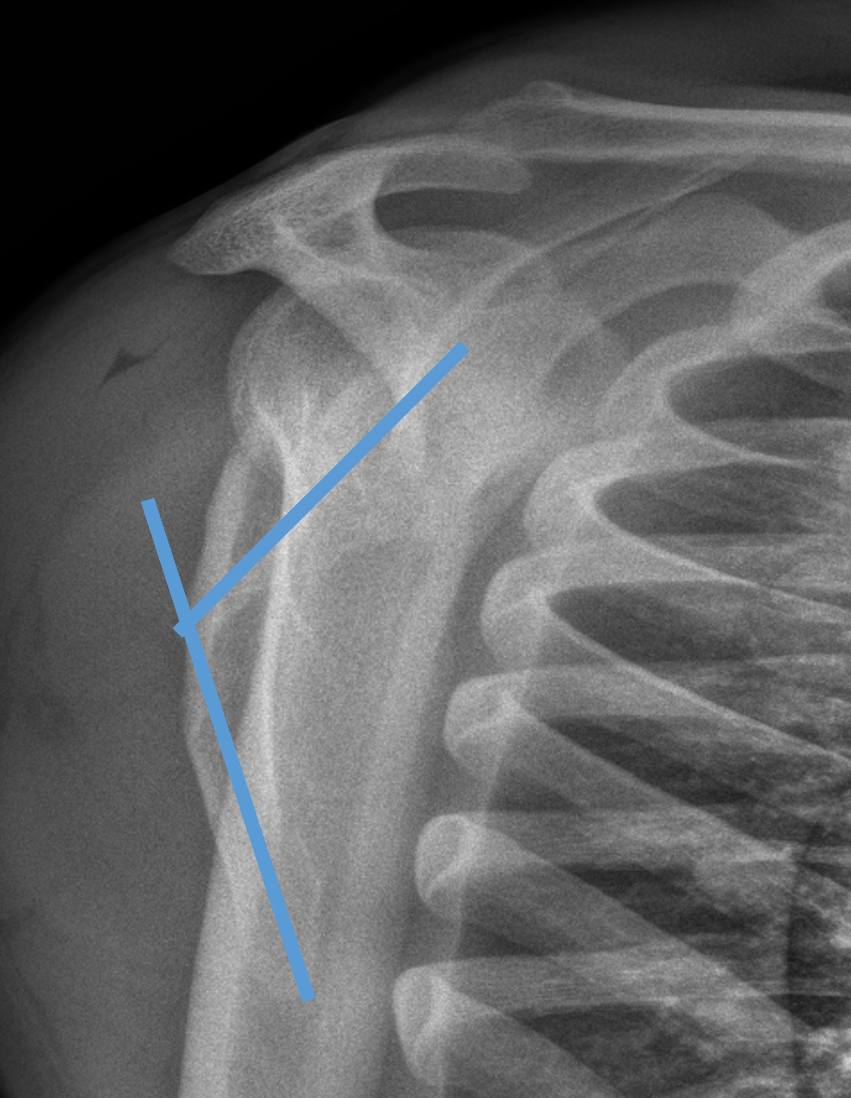

| Glenoid neck displacement | Glenoid neck angulation | Glenopolar angle |

|---|---|---|

| > 2cm medial displacement | > 45° angular deformity | < 22° glenopolar angle |

Angulation